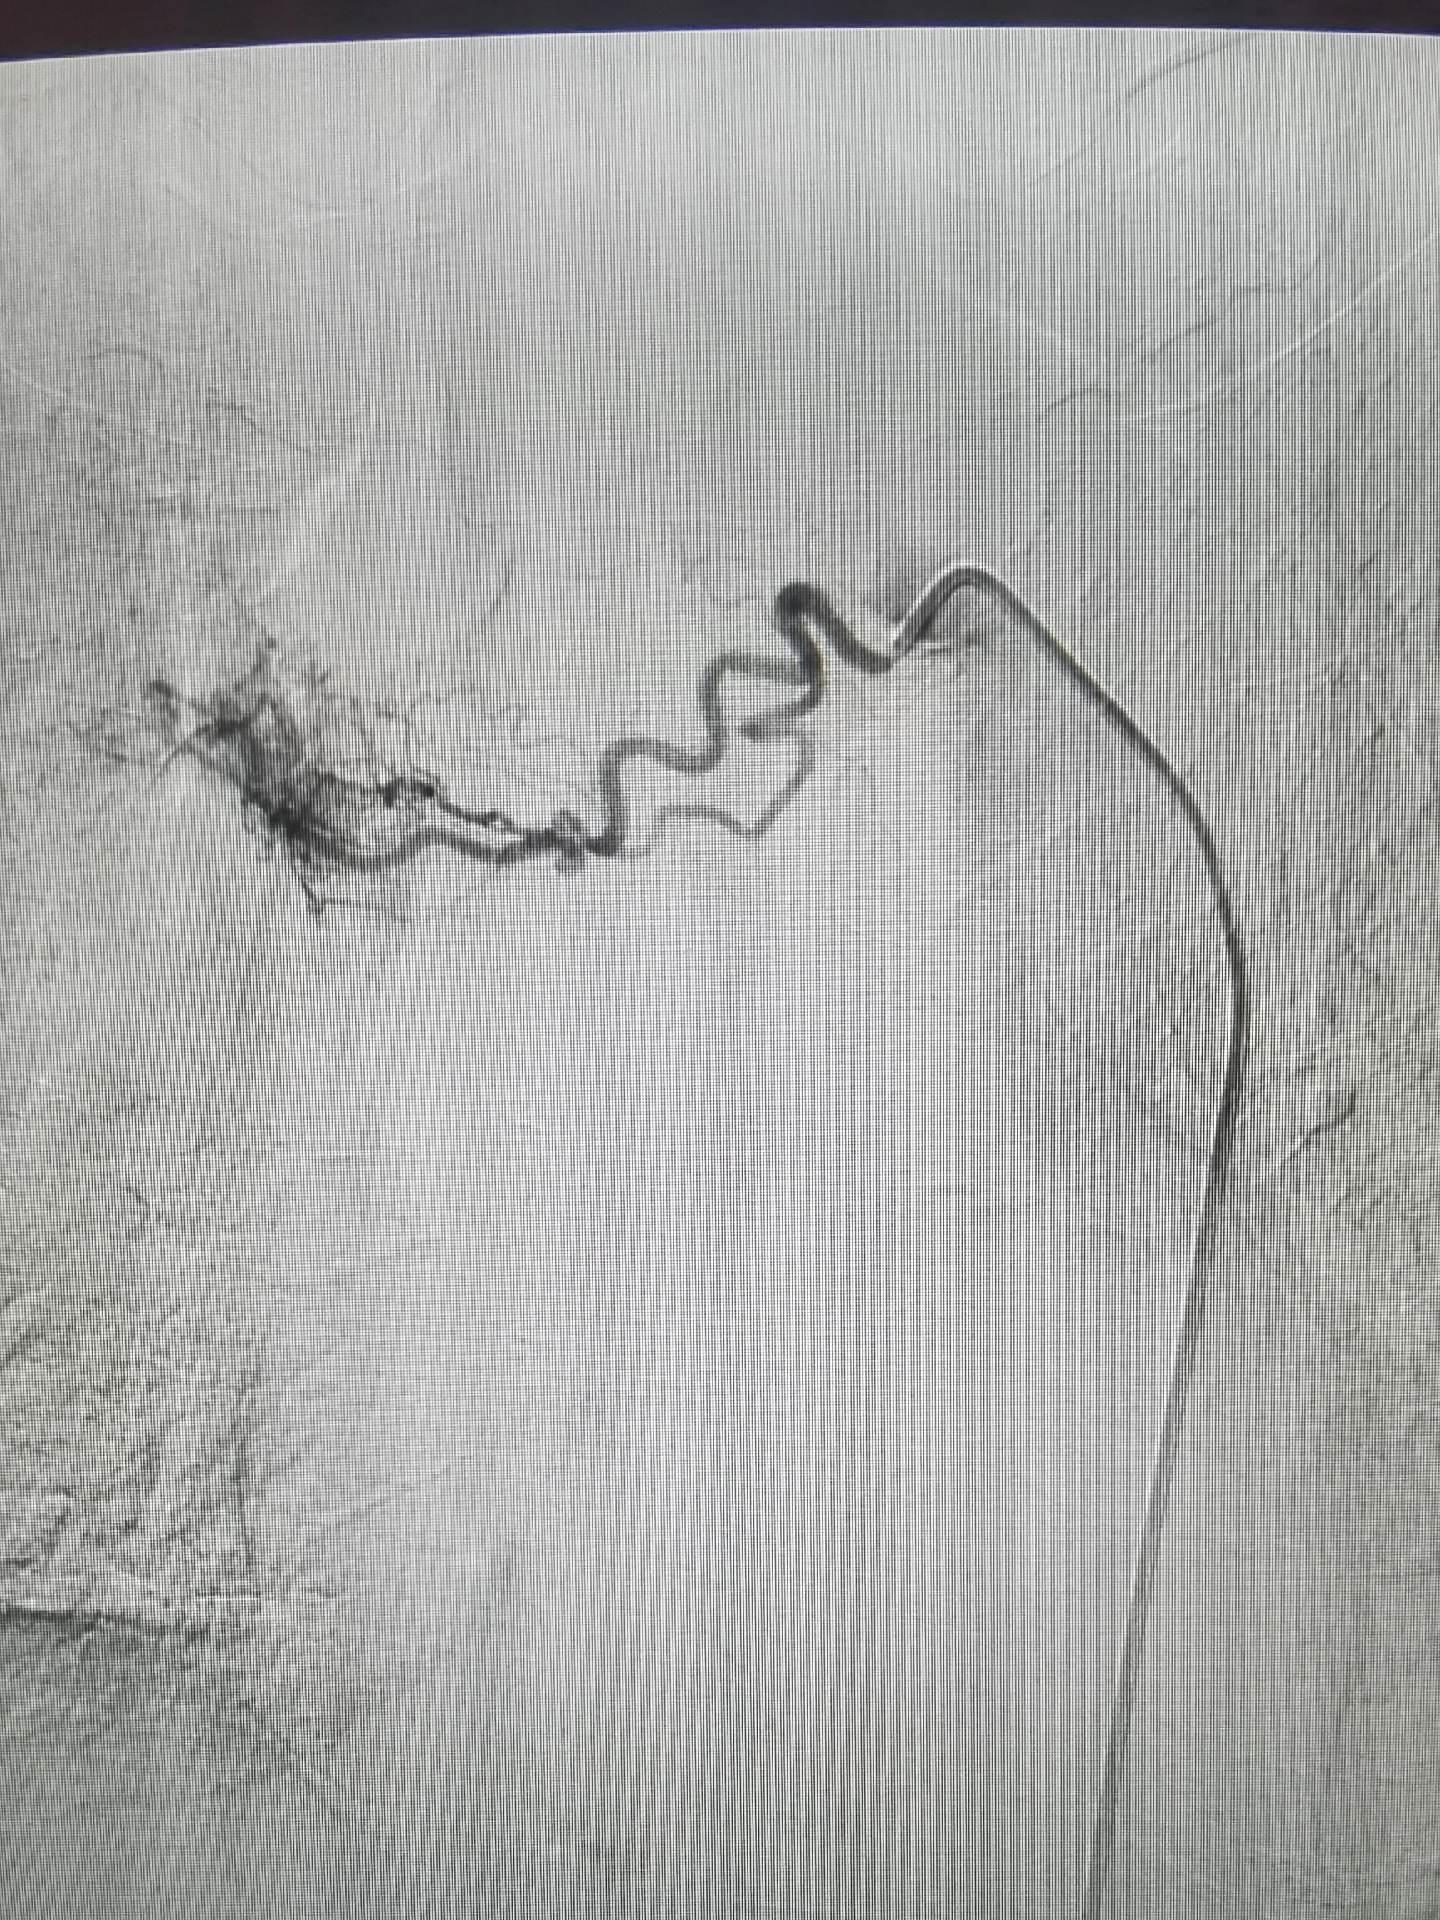

急诊咯血介入治疗,胸上动脉,锁骨下动脉分支,右侧支肋共干支气管动脉,右侧支气管动脉,食管固有动脉,左侧支气管动脉,右侧膈动脉,术前CTA以及选择合适的大导管和微导管真的重要,不仅能超选到位,又能快速完成超选。